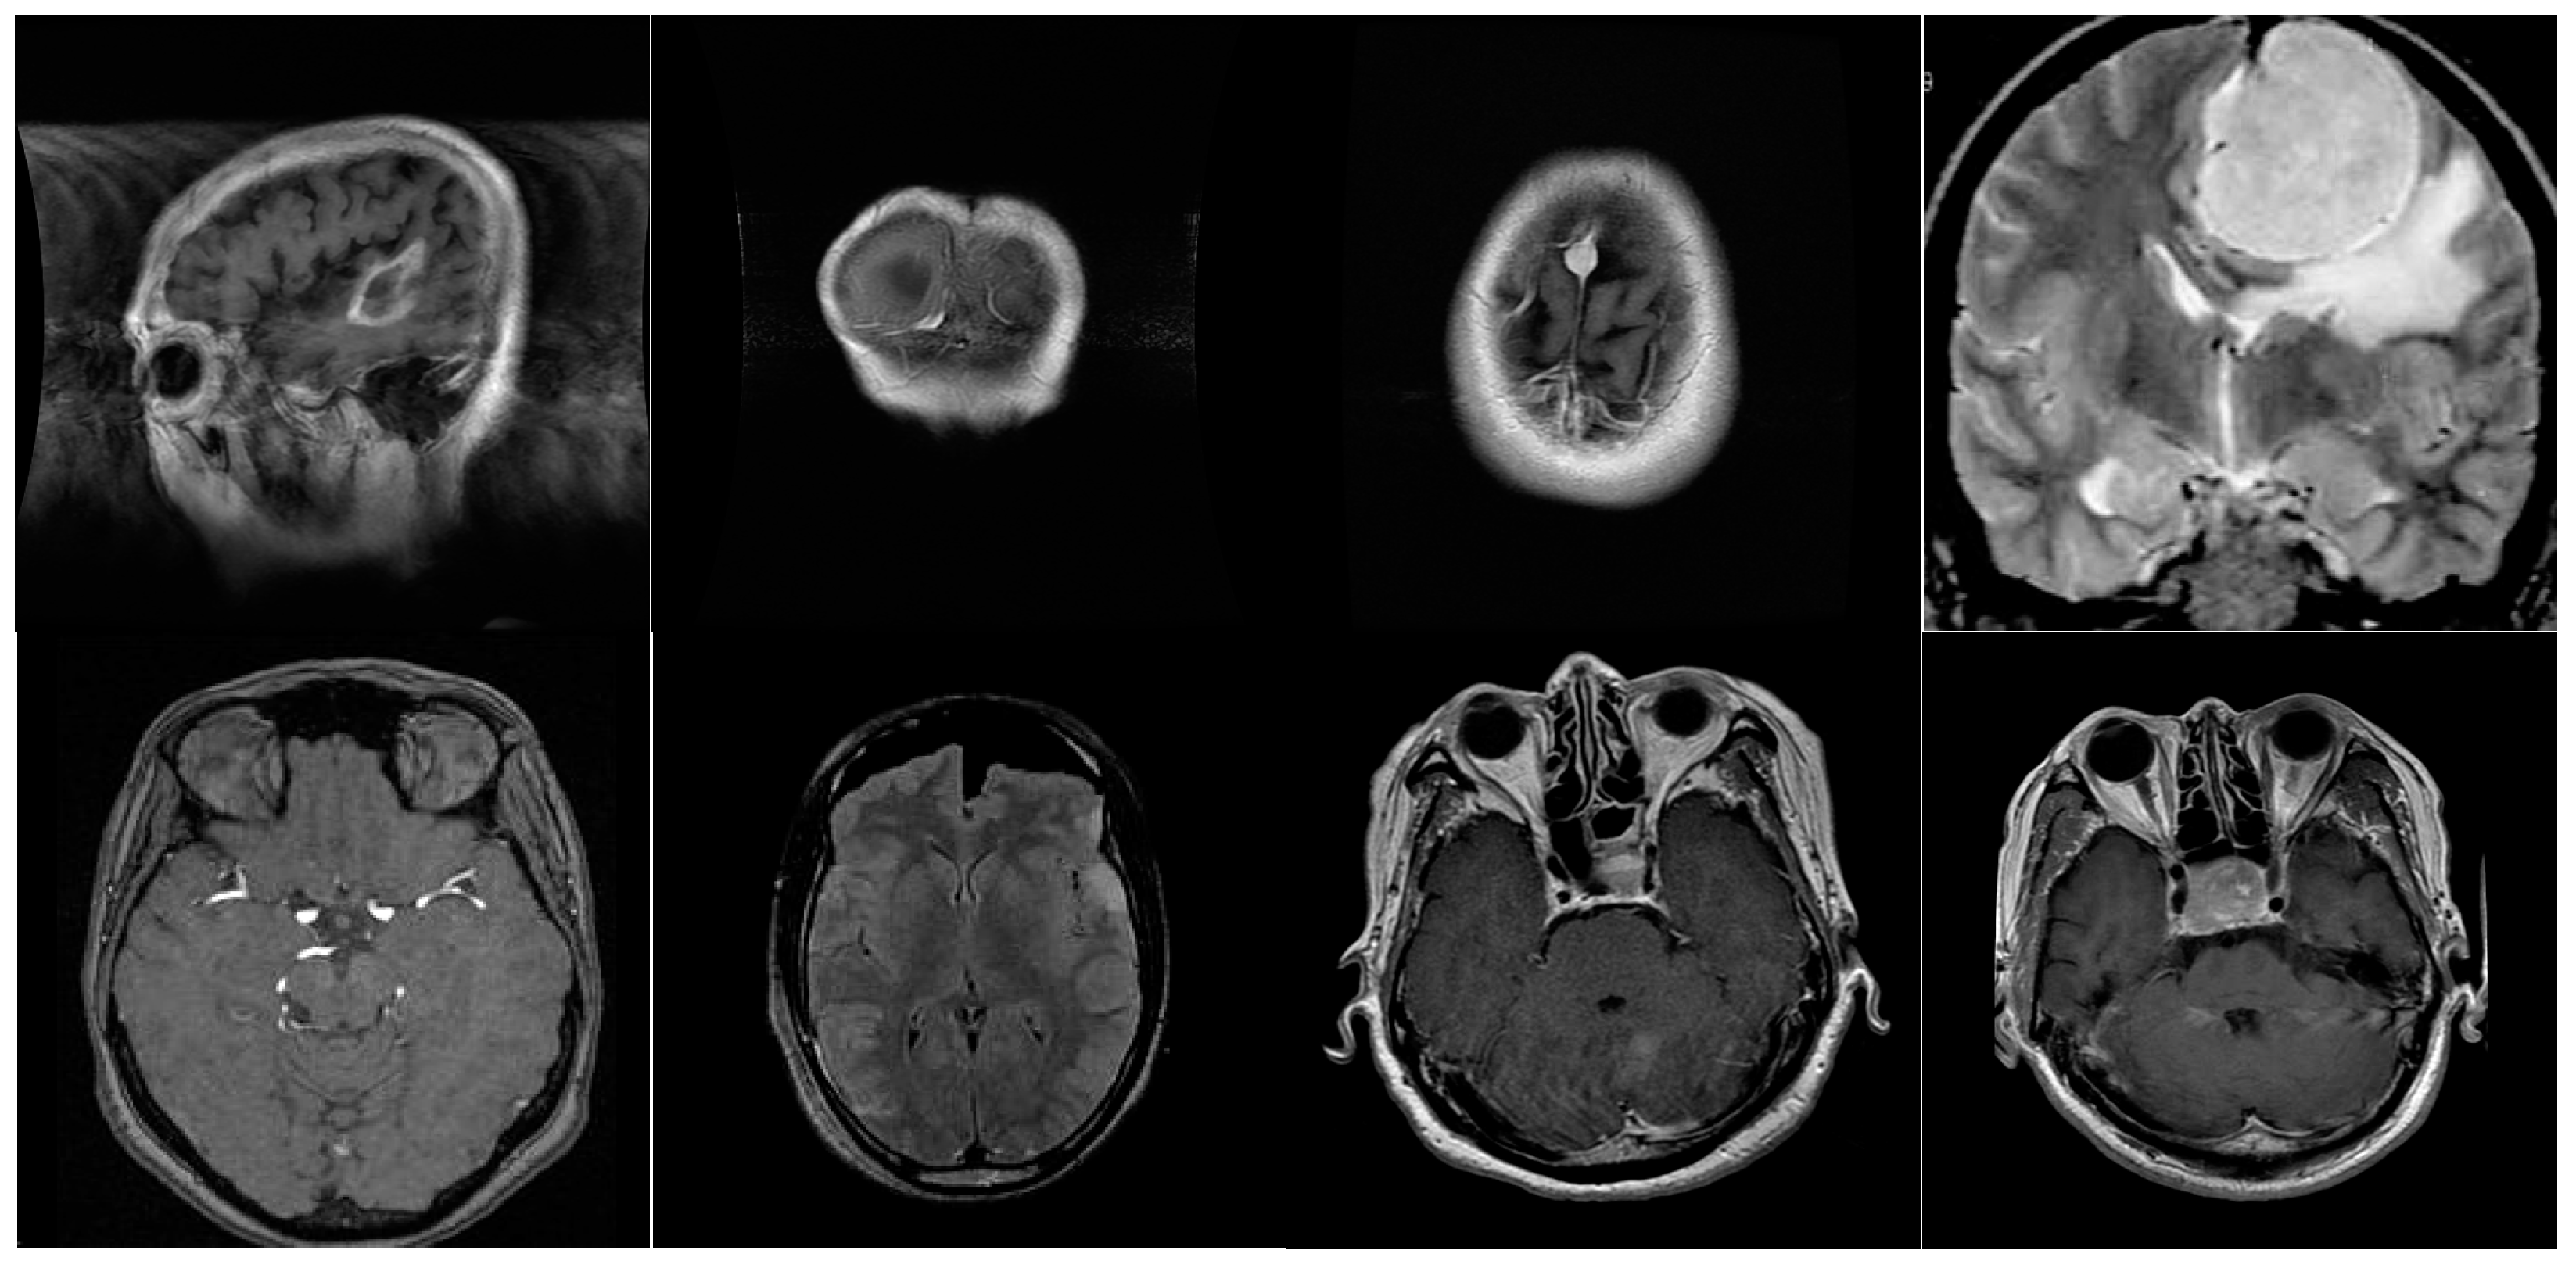

2.1. Dataset